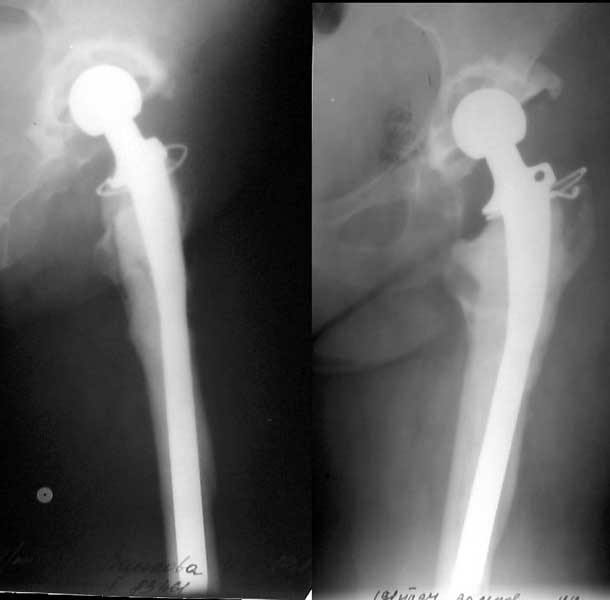

A female (birthdate 1948) was operated in 1995 because of the hip arthritis - THA (Phoenix). 1997 - revision THA with a cement Beznoska (the images attached). Recent weeks she marked pain in the femur and instability - xrays revealed stem migration and shaft fracture.

Looking at the images your patient has an eggshell like bone filled with cement and prosthesis in the upper half. A longer stem would eventually land in a distal fracture, I feel. After you do removal of components, nailing and bone grafting why don't you keep her on traction and treat like an excision arthroplasty. This could be lesser of the evils. (Already two hip surgeries with one revision and one shaft fracture in seven years at the age of 54 years). An interesting problem for Surgeons from less developed countries since we can't go on revising hips forever due to non availability of components and economics.